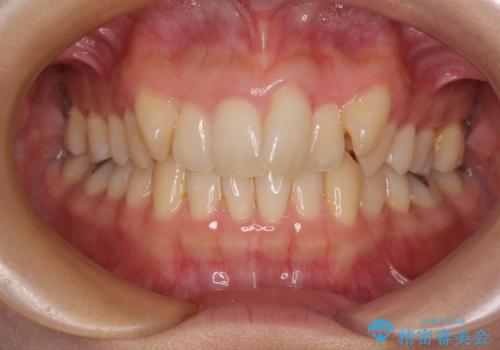

[ マウスピース矯正] 前歯のがたつき 出っ歯に見える歯をきれいに

![[ マウスピース矯正] 前歯のがたつき 出っ歯に見える歯をきれいに の症例 治療前](https://seimitsushinbi.jp/wp/wp-content/uploads/2025/04/IMG_0123-500x350.jpg?v=1744960747)